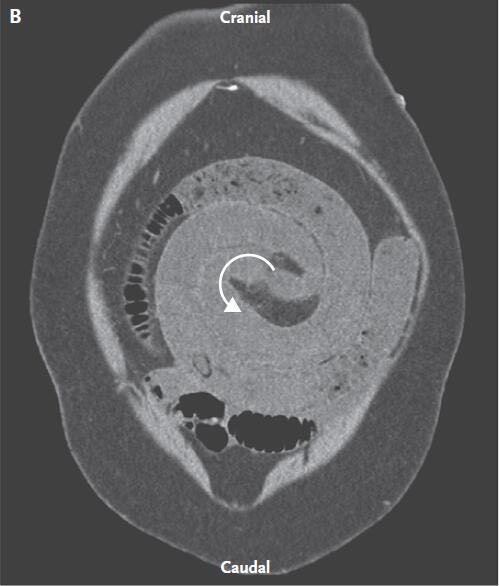

体格检查期间,该例患者心动过速、呼吸急促。 腹部检查显示腹部鼓起,膨胀,伴有严重全身性腹部压痛,反跳痛与腹膜炎表现一致。 放射X线(图A)和计算机断层扫描(CT)(图B)显示小肠呈环型扩张远端接近吻合术缝合线,近端压力降低。 通过CT可明显观察到,肠和肠系膜血管旋转,当它们穿过肠系膜空肠吻合术肠系膜缺损时形成小肠腹内疝。腹腔镜探查显示小肠腹内疝。通过处理,减小疝囊,缺损闭合。